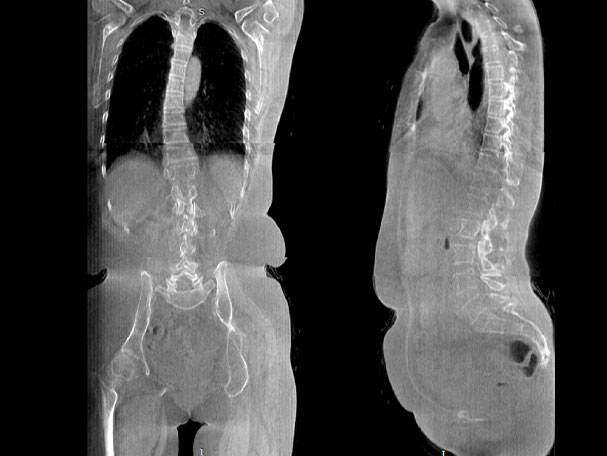

填补常规CT/MR空白

助力术前规划和术后评估